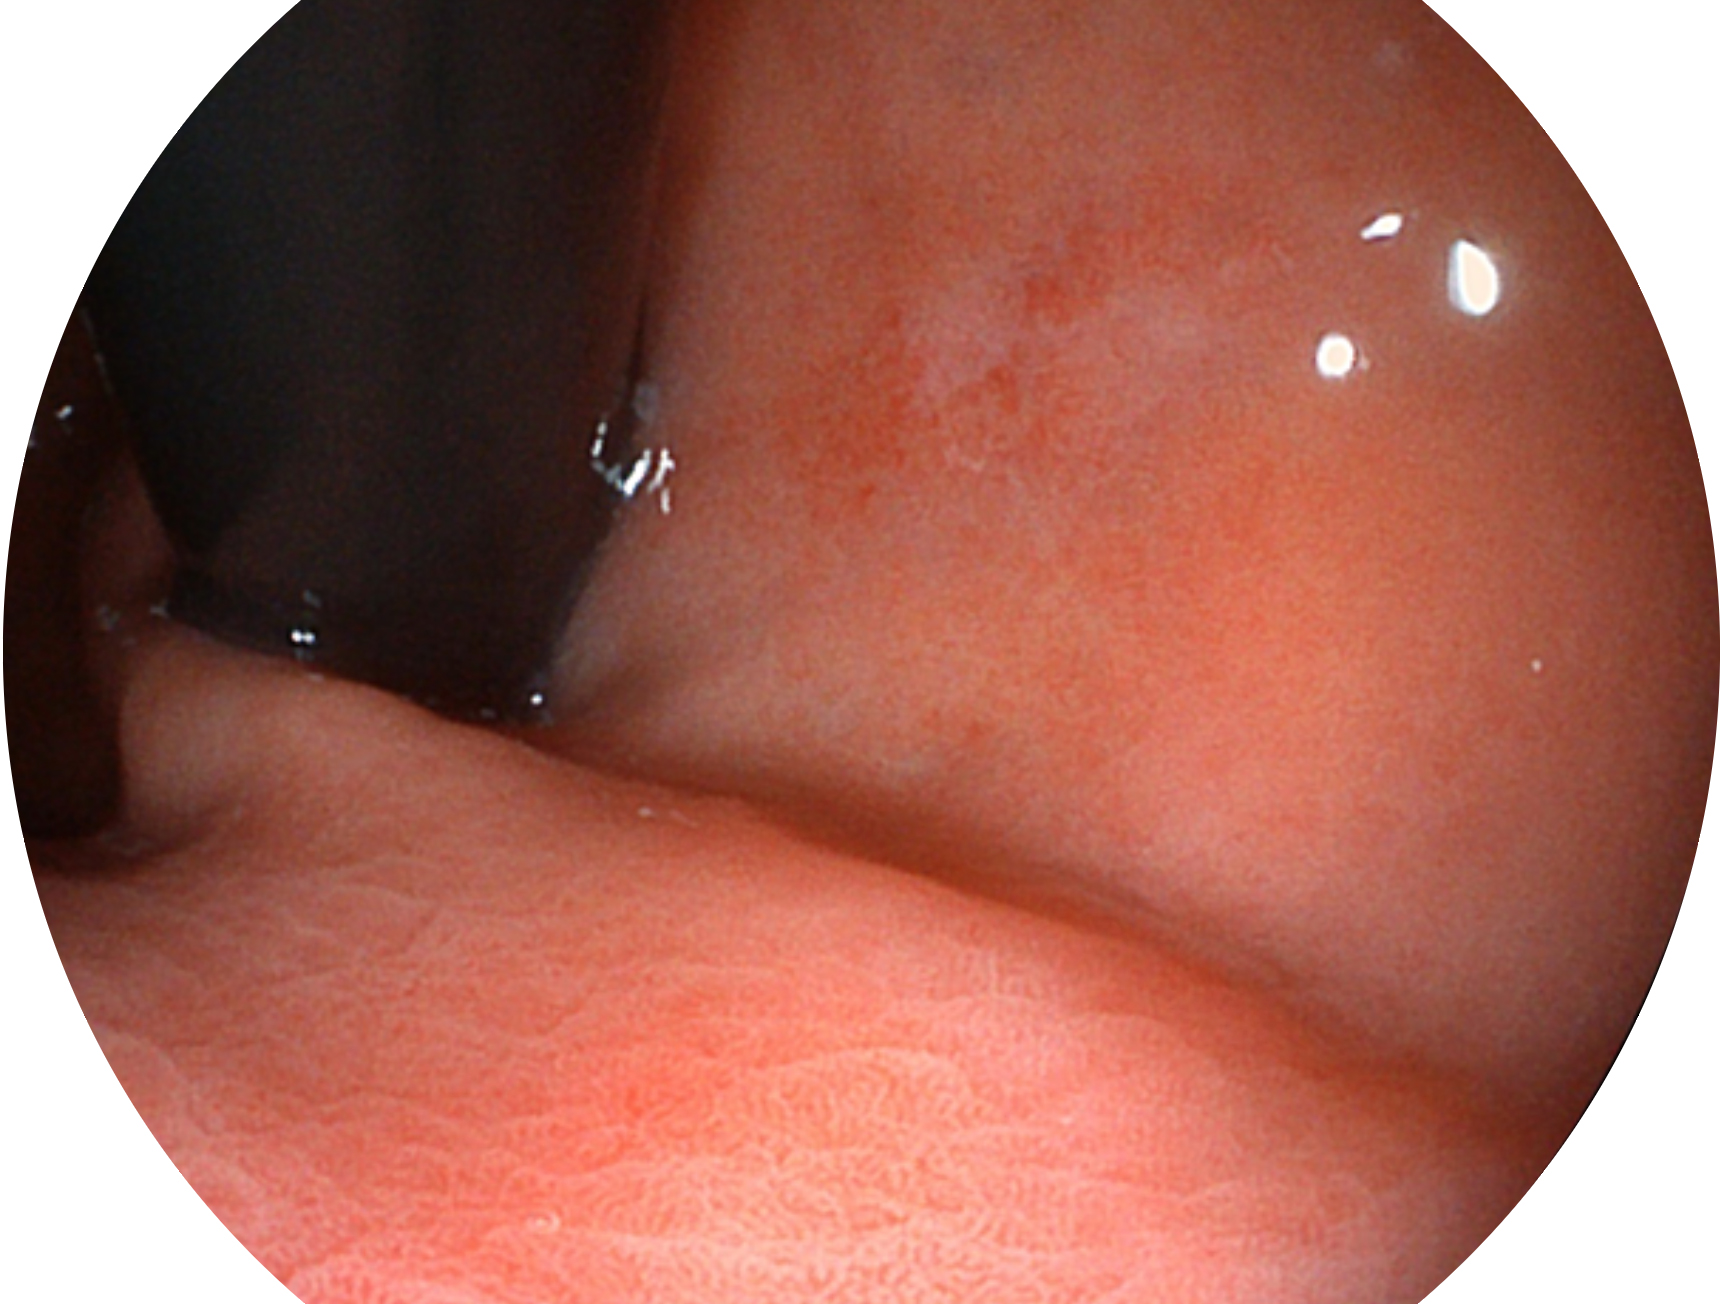

竞技宝(JJB)官方网站新开发的内镜染色技术,主要是基于多波长LED 光源的开发,VLS-55Q 四波长LED 光源是由四个不同颜色的LED光按照相应照明模式所规定的特定发光比例进行合束后形成,合束后形成的照明光的光谱由红光、绿光、蓝光及蓝紫光这四个不同的波段范围构成。具有更高光谱自由度,通过光谱比例的控制,实现了聚谱成像技术,英文全称为“Spectral Focused Imaging, SFI”,缩写为“SFI”和光电复合染色成像技术,英文全称为“Versatile Intelligent Staining Technology, VIST”,缩写为“VIST”。